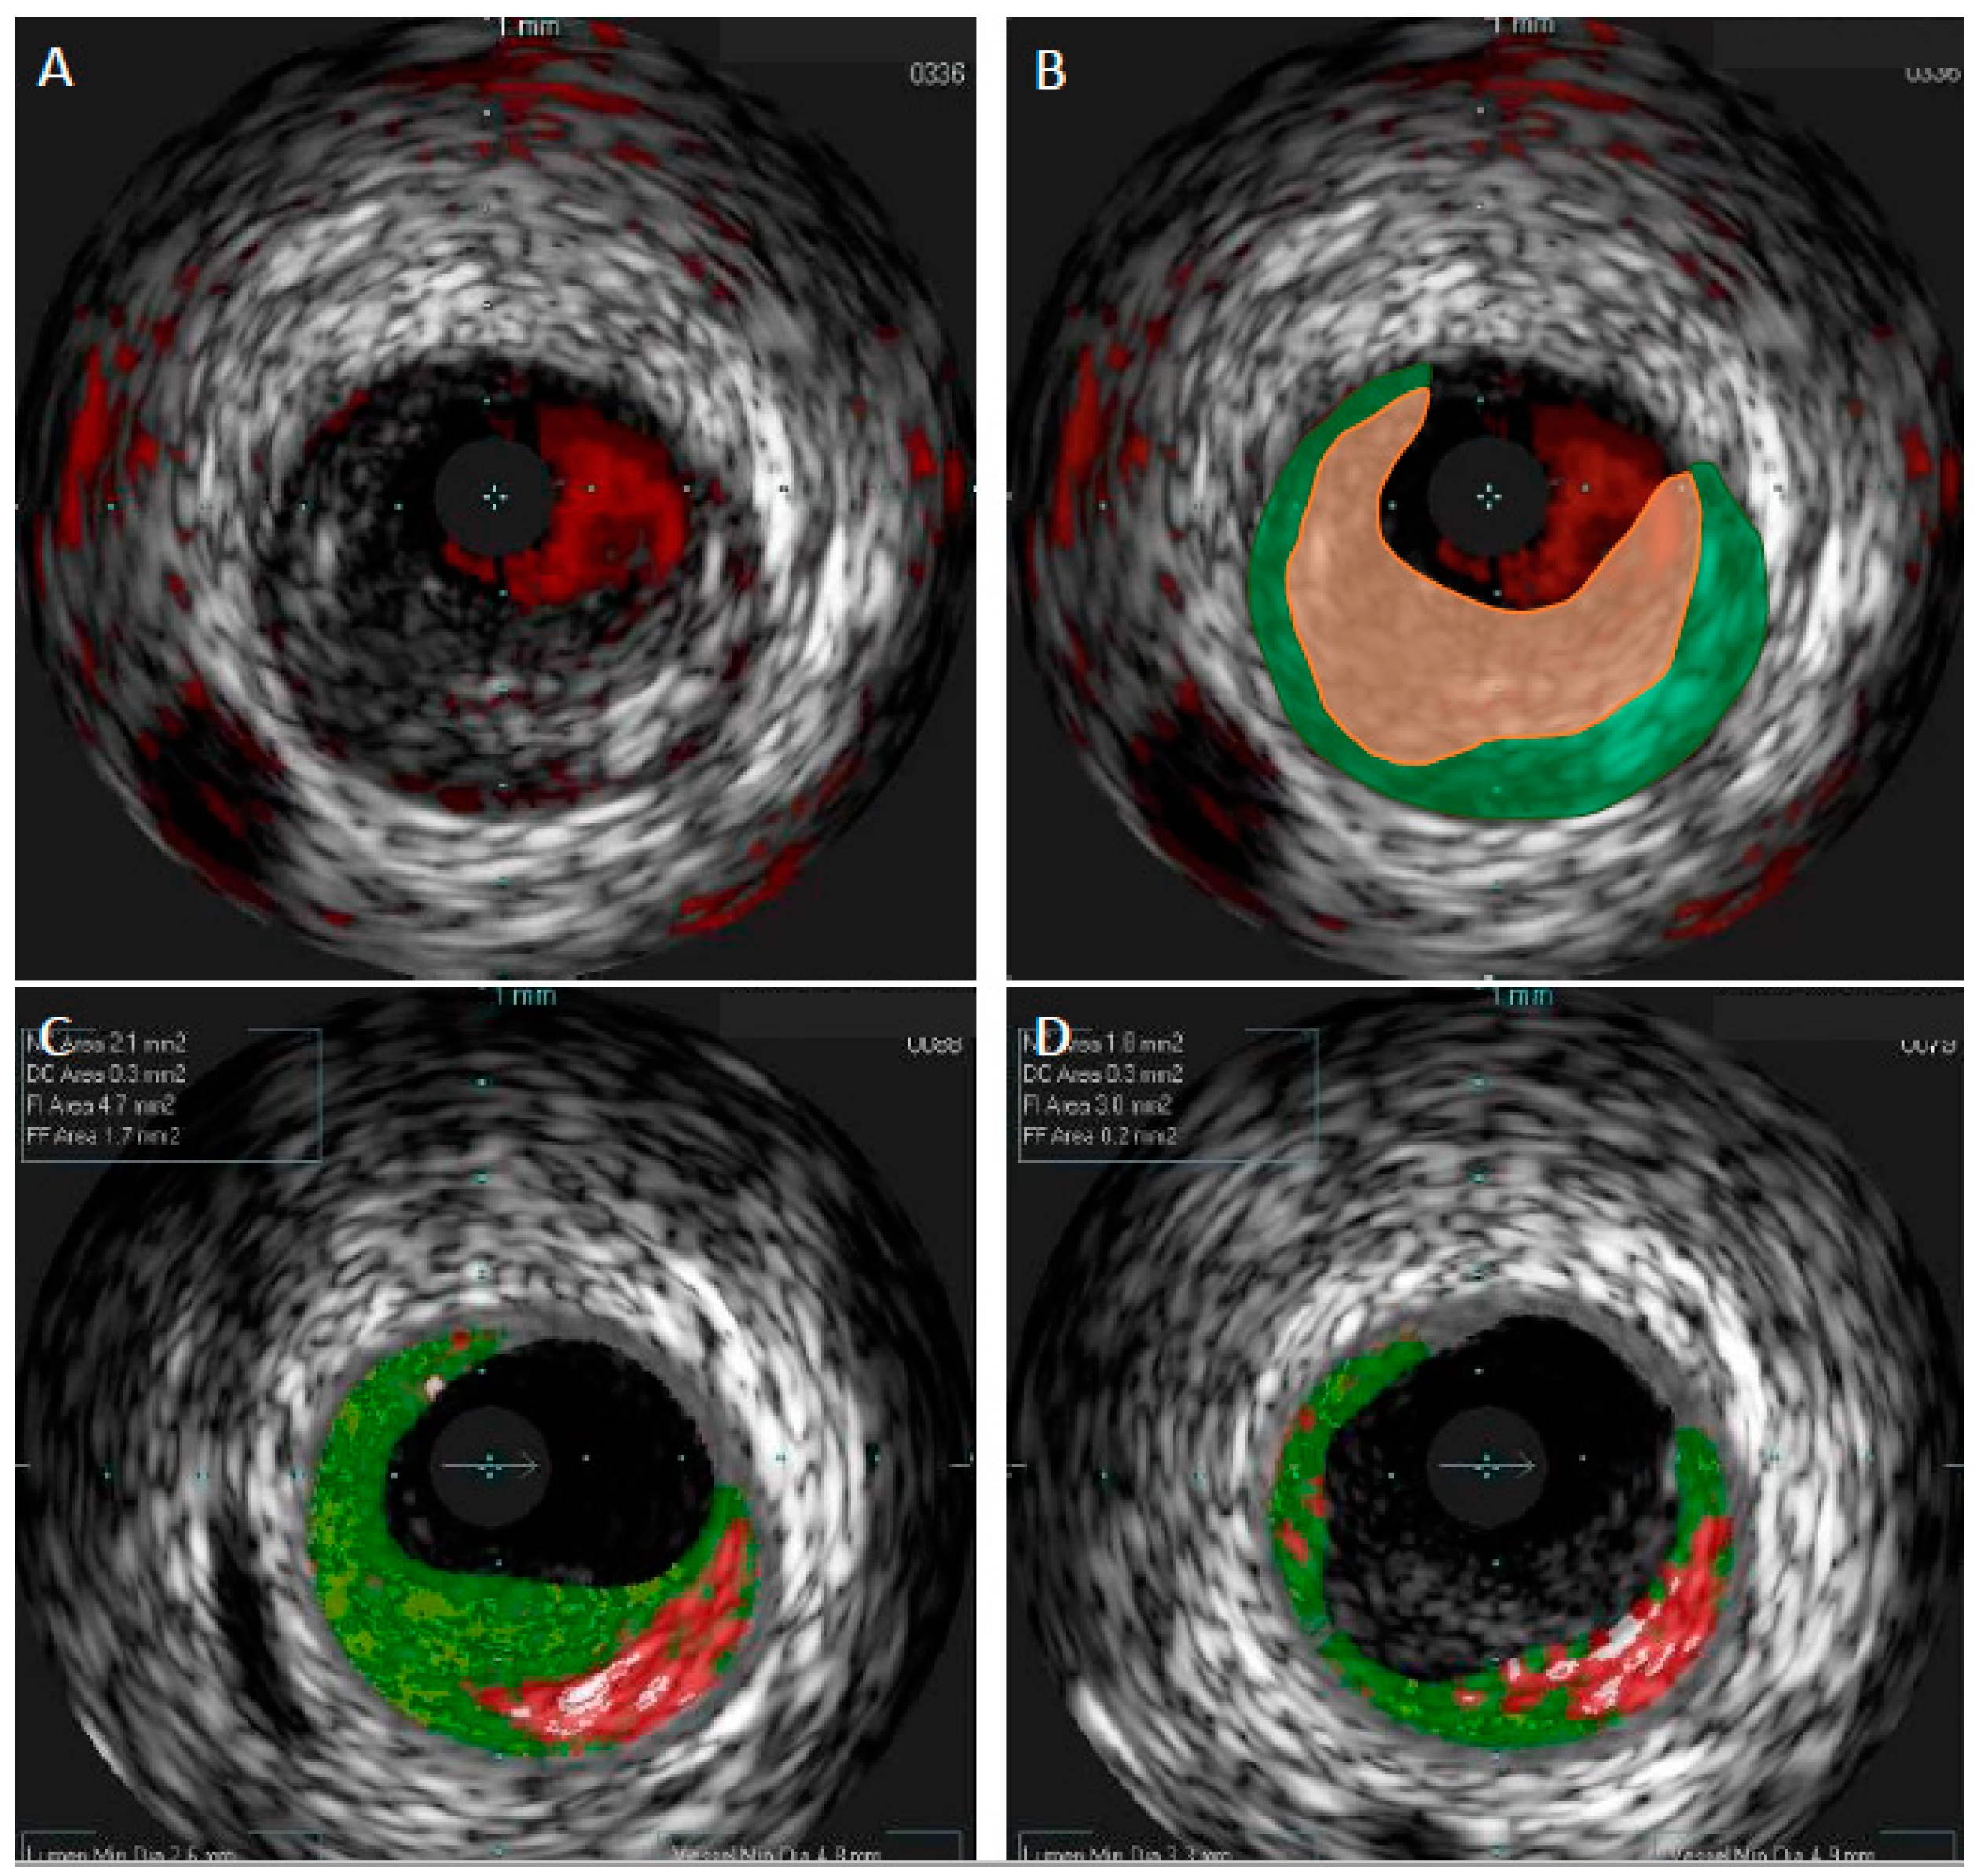

Color coding of the four histological tissue subtypes in VH-IVUS allowed for a swift recognition of the plaque composition: fibrous (green); fibrofatty (yellow); necrotic core (red); and calcified (white) [20]. Histological validation demonstrated satisfactory accuracy for this technique ranging between 79.7% and 96.5% depending on the tissue type and study [19,21]. Importantly, the introduction of VH-IVUS allowed for the indirect detection of TCFA. Although VH-IVUS did not have a resolution high enough for direct imaging of TCFA, the definition of VH-TCFA was proposed in order to facilitate this problem. Presence of ≥10% of necrotic core volume without overlying fibrous tissue and with plaque burden ≥40% for three consecutive frames, which was defined as VH-TCFA, has been shown to reliably identify TCFA, as assessed by the histopathology in a study by Brown et al. [22]. However, in the same study, eight TCFAs on histopathology were not identified by VH-IVUS properly—seven of them were classified as thick-cap fibroatheromas. The authors concluded that VH-IVUS can identify large areas of NC, but it has difficulties with discriminating thin fibrous caps. It should also be emphasized that, like GS-IVUS, VH-IVUS cannot detect thrombus in coronary arteries. Furthermore, thrombus may be mistaken as fibrotic or fibrofatty plaque by VH-IVUS (Figure 2).

Figure 2.

Comparison of gray-scale intravascular ultrasound and virtual histology intravascular ultrasound in patient with acute coronary syndrome. In gray-scale intravascular ultrasound (GS-IVUS), cross-section with lumen narrowing could be interpreted as soft plaque (A). However, on live image, motion and oscillation of the “plaque” were visible—image typical for thrombus. After postprocessing, thrombus (orange zone) was separated from true plaque (green zone) in GS-IVUS (B). In the same patient virtual histology intravascular ultrasound (VH-IVUS) marked thrombus as fibrotic plaque (C). Only after postprocessing could visualization of real borders of the plaque be presented (D).